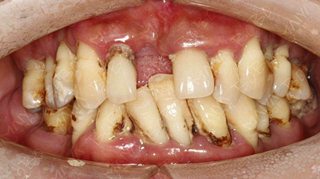

术前牙齿照片

术前照片